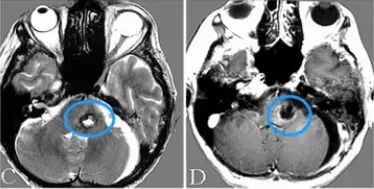

图3:(a)经左外侧裂入路的手术视野。动脉瘤切除术后,动脉瘤夹闭成功,血栓被清除。动脉瘤周围未发现血管。(b&c)术后CT显示脑干解除占位效应,无缺血性病变。

病人的术后过程平安无事,无并发症,神经症状减轻。术后2周3D-CT血管造影证实动脉瘤完全夹闭,血栓完全清除(图3)。患者的神经系统状况有所改善,意识恢复到GCS15(格拉斯哥昏迷指数评分显示意识清醒),右偏瘫好转。术前完全性动眼神经麻痹部分好转。